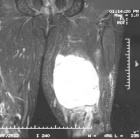

68 year old male with mass noted in left leg four weeks ago

Zoom image: Radiological image Radiological image.